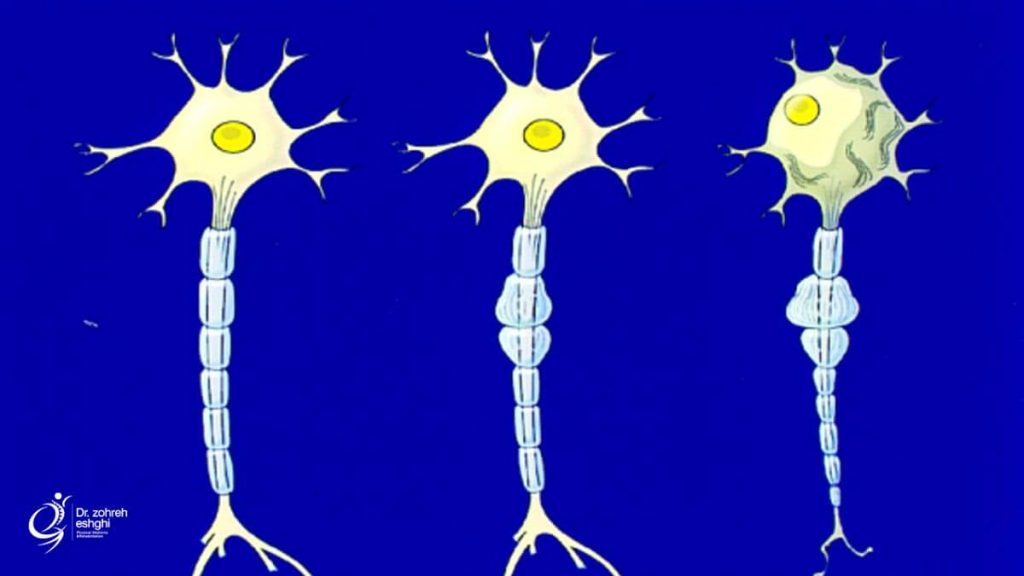

با مرگ سلول های عصبی در بیماری موتور نورون، پیام های الکتریکی نمی توانند از مغز به عضلات برسند. به مرور زمان، عضلات تحلیل می روند. این وضعیت، آتروفی نامیده می شوند.

در این وضعیت، فرد، کنترل حرکات خود را از دست داده و راه رفتن، حرف زدن، بلعیدن و تنفس دشوارتر می شود.

به مرور زمان این عضلات، ضعیف شده و تحلیل می روند. ممکن است فرد در عضلات خود دچار سفتی و کشش ناگهانی نیز شود.

این نوع نسبت به ای ال اس یا PBP شیوع بسیار کمتری داشته می تواند موروثی یا پراکنده باشد. این بیماری به طور عمده نورون های حرکتی تحتانی را درگیر می کند.

معمولا ضعف در دست ها آغاز شده و سپس به دیگر بخش های بدن گسترش می یابد. عضلات، ضعیف شده و گاهی دچار گرفتگی می شوند. این بیماری می تواند به ای ال اس تبدیل شود.